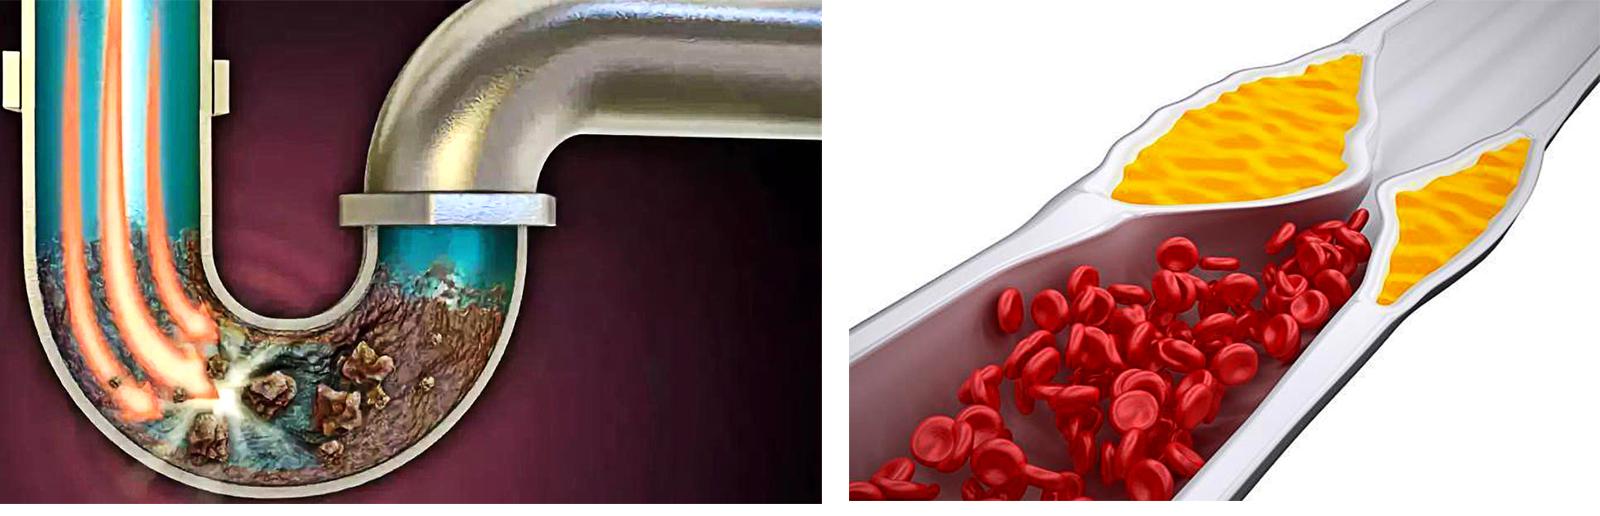

商業ビルを例にとると、高層階の居住者は脳細胞に、低層階から高層階への配管は血管に例えられる。

水道管が錆びたり、老朽化したり、汚れが溜まって管腔が狭くなったり、あるいは詰まったりすると、水は上の階まで流れなくなる。想像してみてほしい。本来10世帯に供給されていた水が、水流が細くなったために1世帯しか使えなくなり、他の9世帯が水不足の影響を受ける。

人体を例にとって言えば、水道管の老化は動脈硬化のようなもので、動脈硬化がプラークを生成するのは「さび色の斑点」、「汚れ」のようなものだ。

違いは、プラークが破裂して血栓症を促進する可能性があることで、これが心血管疾患の急性発作の原因である。